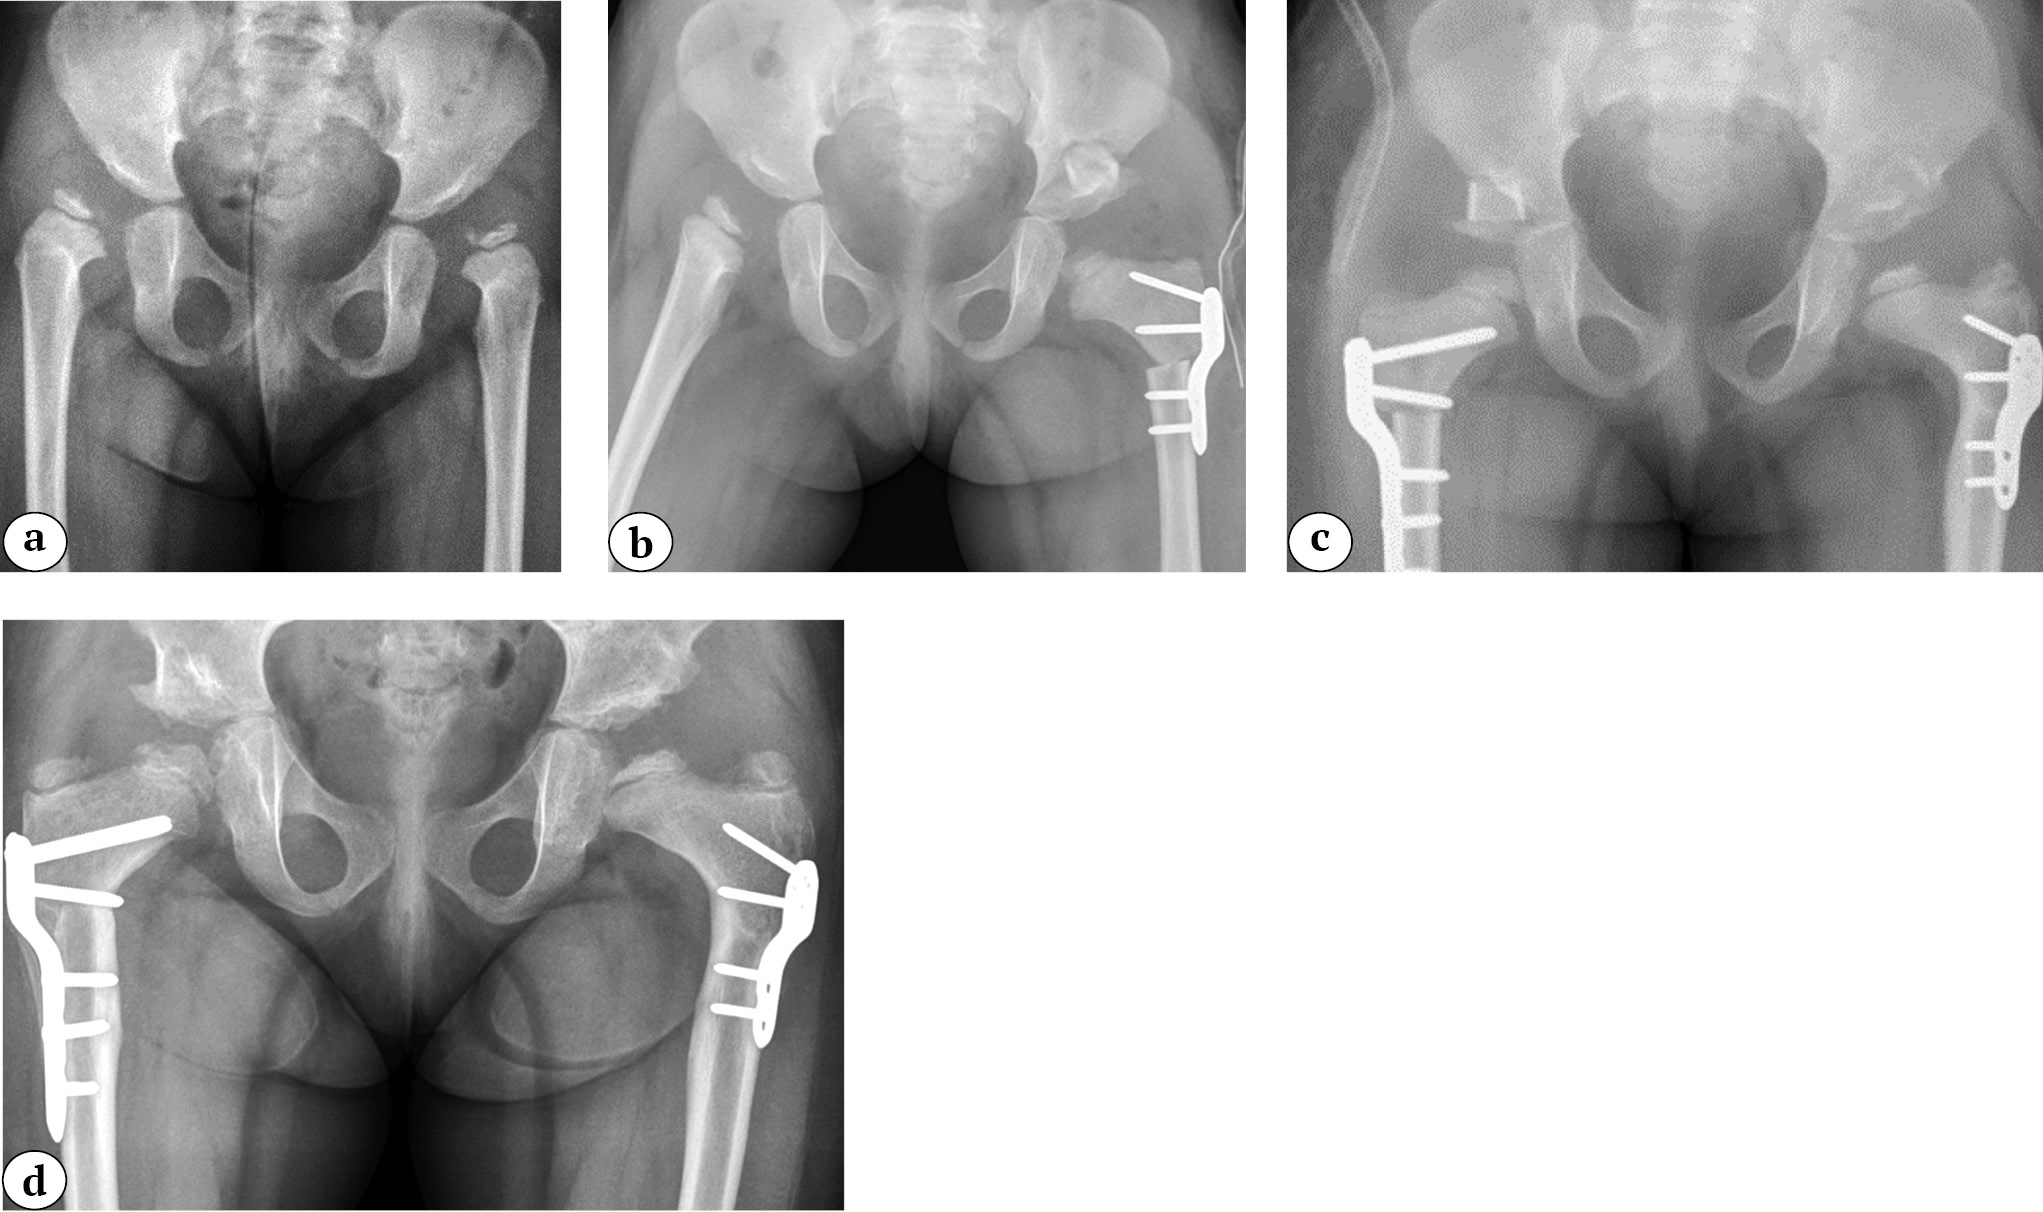

В результате варизирующей деротационной остеотомии бедра произошло снижение значения ШДУ с 143,62±2,97° до 110,53±3,44° (p = 0,00160). АНГБК наблюдался в 4 случаях (30,1%) у 3 детей (25%), включая пациента, которому была выполнена операция с двух сторон (рис. 3). На последнем осмотре ШДУ увеличился до 119,11±6,82° (p = 0,03765) у 9 пациентов, у которых не было отмечено развития АНГБК, и уменьшился до 87,7±31,3° (p не определялся из-за маленькой выборки) у 3 пациентов с АНГБК. У одного пациента с АНГБК отмечено развитие медиального вывиха головки бедренной кости из-за прогрессирующей варусной деформации до 41° (рис. 4).

Рис. 3. Рентгенограммы пациентки в возрасте 2 лет 5 мес. До операции: двусторонний вывих тазобедренных суставов (III степень дисплазии по классификации IHDI билатерально) (a); после первой операции: вывих левого тазобедренного сустава устранен, выполнена варизирующая остеотомия бедренной кости, фиксация 2,7 мм LCP пластиной и ацетабулопластика по Dega (b); через 10 мес. после второй операции: вывих правого тазобедренного сустава устранен, выполнена варизирующая остеотомия бедренной кости, фиксация 3,5 мм LCP пластиной и ацетабулопластика по Dega (c); развитие аваскулярного некроза билатерально через 2 года и 5 мес. после первой операции (d)

Fig. 3. X-rays of the patient aged 2 years and 5 months. Before the first operation: bilateral dislocation of the hip (Grade III dysplasia according to IHDI classification) (a); after the first operation: dislocation of the left hip is corrected, varus osteotomy of the femur is performed, fixation with a 2.7 mm LCP plate, and acetabuloplasty according to the Dega technique (b); 10 months after the second operation: dislocation of the right hip is corrected, varus osteotomy of the femur is performed, fixation with a 3.5 mm LCP plate, and acetabuloplasty according to the Dega technique (c); development of avascular necrosis bilaterally 2 years and 5 months after the first operation (d)